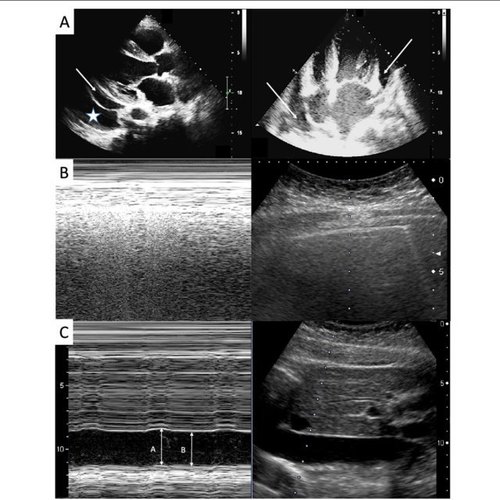

Toshiba Aplio MX keeps up some decent features that deliver some nice pictures (Differential Tissue Harmonics, Aplipure, and Precision Imaging), produce quicker and faster results (One-contact Quick scan) and eventually expand the general nature of tests (IASSIST™) through the management of workflow. The fine detail in Toshiba’s product offering makes it exceptionally alluring and attractive to use in hospitals, clinics, multi-doctor practices.

AplioMx features used in applications:

- Obstetrics

- Gynecology

- Vascular

- Urology

- MSK

- Cardiac

- TEE

- 4D